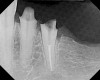

Figure 14  The preoperative radiograph showed an overhanging margin that was in close proximity to the bony crest.

Figure 14